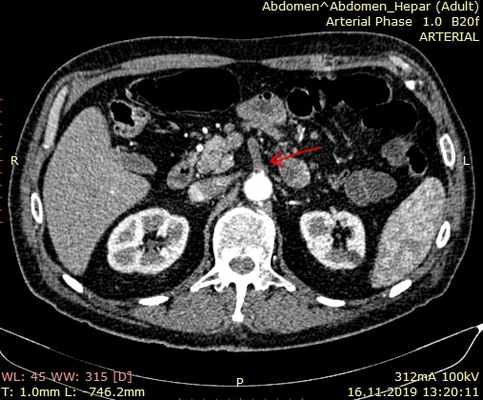

![МСКТ ангиография при остром тромбозе верхней брыжеечной артерии]()

Мультиспиральная компьютерная томография с ангиографией

Мультиспиральная компьютерная томография аорты и ее ветвей позволяет точно оценить состоянии брыжеечных сосудов и помочь правильной постановке диагноза. Признаками острой мезентериальной непроходимости является отсутствие контрастирования брыжеечных артерий со слабым развитием коллатеральных сетей кровообращения. При соответствующих жалобах и клинической картине компьютерная томография позволяет поставить точный диагноз в большинстве случаев мезентериального тромбоза. Требуется внутривенное введение контраста и детальный анализ полученных изображений.